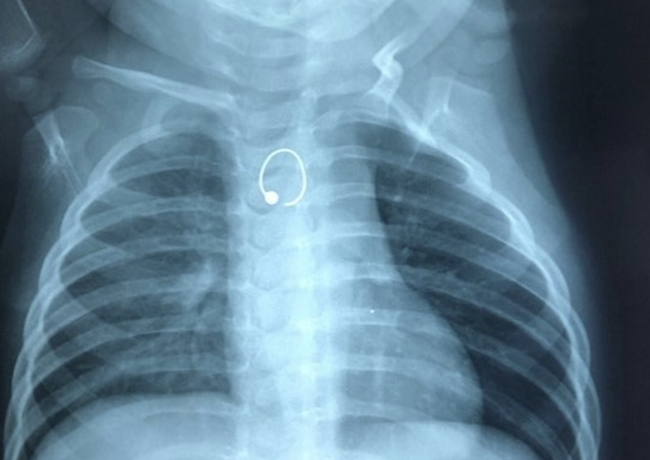

22/07/2020 22:43Bé gái 10 tháng tuổi suýt chết vì nuốt phải bông tai vàng sắc nhọn

Người nhà khai cách nhập viện 3 tuần bé khò khè khi bú và khi ngủ, tự mua thuốc uống. Sau đó 1 tuần thì bé thở mệt hơn không sốt, bú kém, được điều trị tại BV tỉnh nhưng không cải thiện.

Vì bé đã từng chẩn đoán suyễn 2 lần tại BV tỉnh và điểu trị có kết quả tốt nên lần này, BS vẫn điều trị suyễn tiếp tục.

Cách nhập viện 1 tuần, bé thở mệt hơn kèm khò khè và bú ít lại. Khi đến khám tại BV địa phương, bé không giảm triệu chứng và chụp X-quang. Ảnh chụp nghi ngờ có dị vật cản quang vùng thực quản.

Sau khi được chuyển đến BV Nhi Đồng 1, các bác sĩ đã tiến hành gây mê soi cấp cứu và gắp được chiếc bông tai cách miệng thực quản khoảng 12cm. Bông tai có 1 đầu như chiếc kim gâm vào thành thực quản nên rất khó di chuyển.

Khi lấy bông tai ra, thực quản bị trầy sướt, chảy máu lượng ít và được cầm máu tại chỗ bằng bông gòn. Hậu can thiệp, bé đã tỉnh táo, được nuôi ăn qua ống sonde dạ dày, không nôn ói, không sốt, không đau.

ThS.BS Phú Quốc Việt, BV Nhi Đồng 1 cho biết, việc hóc các loại dị vật như vật dụng, đồ chơi, đồng xu, pin...ở trẻ nhỏ rất thường gặp tại đây.

Tình trạng này nguy hiểm vô cùng, có thể dẫn đến các biến chứng nguy hiểm như không ăn uống được, áp xe thành sau họng, áp xe cổ, áp xe – thủng thực quản, tổn thương mạch máu...

"Việc hóc dị vật là kim loại mà lại phát hiện rất trễ là trường hợp rất lạ, có thể do ngay từ đầu triệu chứng giống với suyễn nên được điều trị theo tiền sử bệnh, đến khi bệnh nặng mới tầm soát các nguy cơ" - bác sĩ nói.

Bác sĩ khuyến cáo những trường hợp bệnh nhân điều trị lâu ngày nếu không cải thiện triệu chứng nên được đưa đến BV để tránh bỏ sót bệnh, tránh các biến chứng đáng tiếc xảy ra.